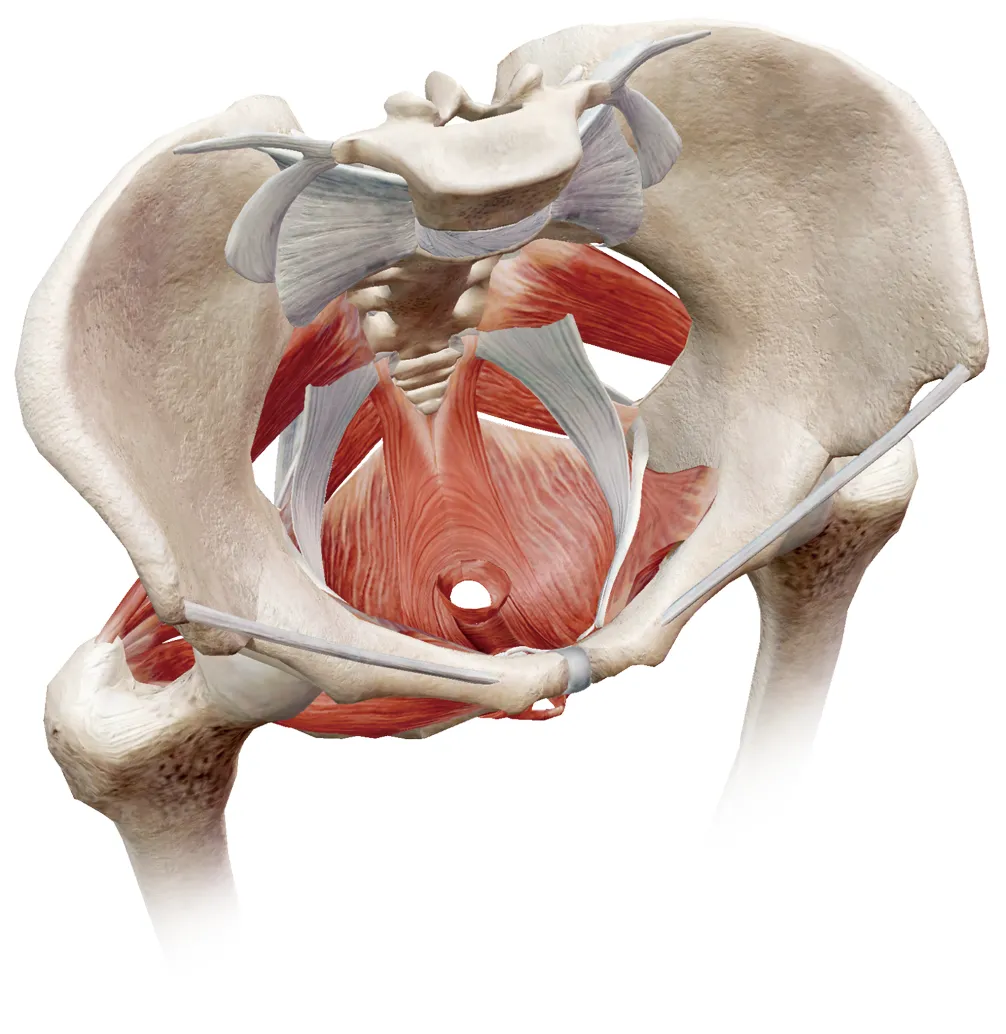

نقش عضلات کف لگن در فرآیند دفع

کف لگن مجموعهای از عضلات است که در بخش پایینی لگن قرار دارد و وظیفه کنترل دفع، حمایت از اندامهای داخلی و هماهنگی عضلانی را برعهده دارد. عملکرد صحیح این عضلات، نقش کلیدی در اجابت مزاج طبیعی دارد.

کف لگن سالم چگونه به دفع کمک میکند؟

در فرآیند دفع، عضلات کف لگن باید همزمان با افزایش فشار شکمی، بهدرستی شل شوند. این هماهنگی به خروج آسان مدفوع کمک میکند.

اختلال عملکرد کف لگن چیست؟

در برخی افراد، این هماهنگی بهدرستی انجام نمیشود. عضلات کف لگن بهجای شل شدن، منقبض میشوند و مسیر دفع را تنگتر میکنند؛ وضعیتی که به آن اختلال عملکرد کف لگن یا دیسسینرژی گفته میشود.